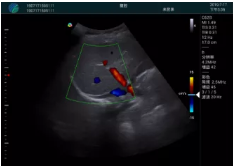

頸動(dòng)脈血流充盈飽滿(mǎn),無(wú)外溢

肝內(nèi)血管顯示清晰,血流敏感無(wú)外溢